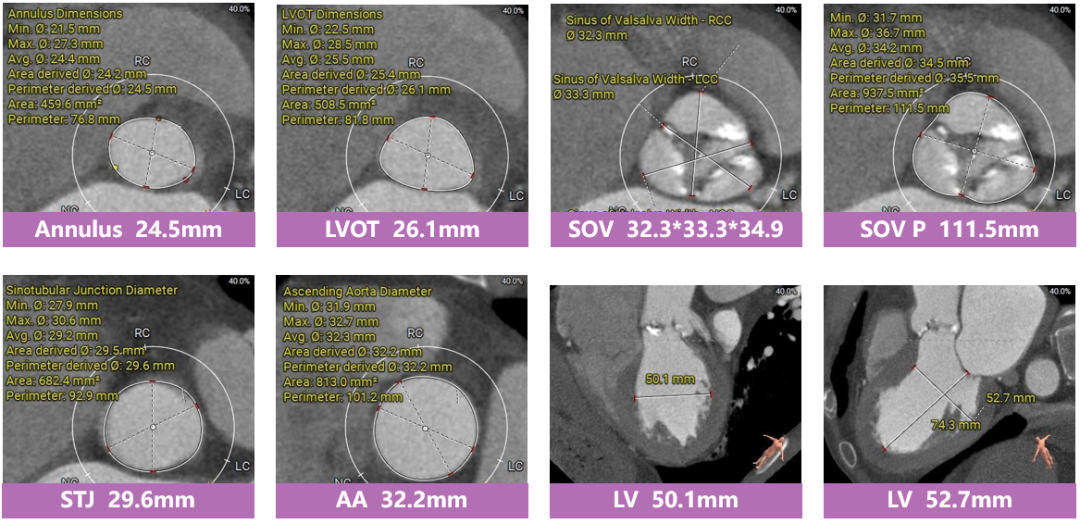

病例一 患者基本信息

女性,73岁。间断胸闷2年余,加重半月,卧位出现喘憋,伴咳嗽,活动耐力下降至2m,超声心动图提示:主动脉瓣峰值流速3.9m/s,峰值压差62mmHg,瓣口面积0.7cm²,EF值34%。主动脉瓣重度狭窄并中量反流,二尖瓣、三尖瓣中量反流;全心增大,升主动脉及主肺动脉宽。

主动脉根部评估

根部概览

钙化概览

功能性二叶瓣,左无钙化融合,心室腔明显扩大。

多平面分析

敞口状流出道,瓣上限制较重,瓣膜释放后存在一定下滑风险。

冠脉分析

左冠开口较低,双侧瓣叶冗长,预估双侧冠脉均存在一定遮挡风险。